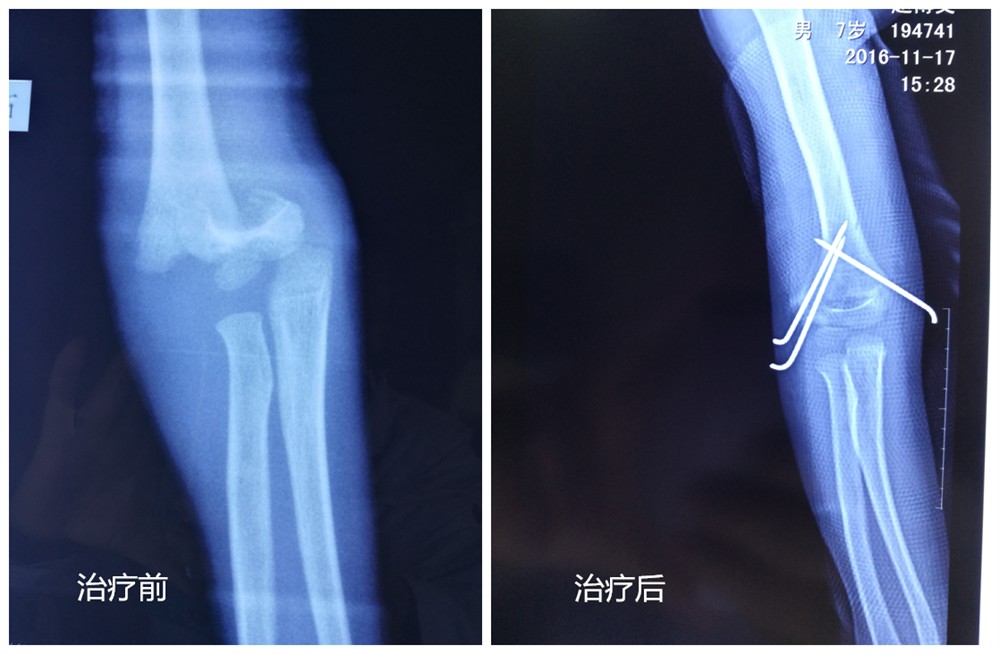

治療前 治療后

湘潭市中醫(yī)醫(yī)院二病室骨傷五科近年來派出多名醫(yī)師前往北京積水潭醫(yī)院、北大人民醫(yī)院骨科進修學習,不斷提高業(yè)務(wù)技術(shù)水平,學習國內(nèi)外先進診療理念并應用于臨床工作中,針對小兒肱骨髁上骨折患者該科室在總結(jié)過去經(jīng)驗教訓的基礎(chǔ)上摸索出了一套適合地市級醫(yī)院的診療方案,近期收治多例“不穩(wěn)定型”肱骨髁上骨折均在外院進行了反復多次的手法整復后骨折復位失敗,出血局部軟組織嚴重腫脹、張力性水泡等并發(fā)癥,來院就診時均為傷后3-5天,由于錯過了最佳治療時期采用常規(guī)手法整復、小夾板固定治療十分困難,如采用開放復位內(nèi)固定很容易導致傷口感染、骨化性肌炎、肘關(guān)節(jié)僵硬等并發(fā)癥,針對這種十分棘手的病例該科室采取了麻醉下閉合復位經(jīng)皮穿針固定的微創(chuàng)治療方案,術(shù)中使用中醫(yī)骨傷科傳統(tǒng)的“拔伸牽引、端提擠按、旋轉(zhuǎn)屈伸”等手法使骨折得到了滿意的復位,術(shù)后配合肘關(guān)節(jié)功能支具進行功能鍛煉,術(shù)后6周患者即得到了滿意的功能恢復。